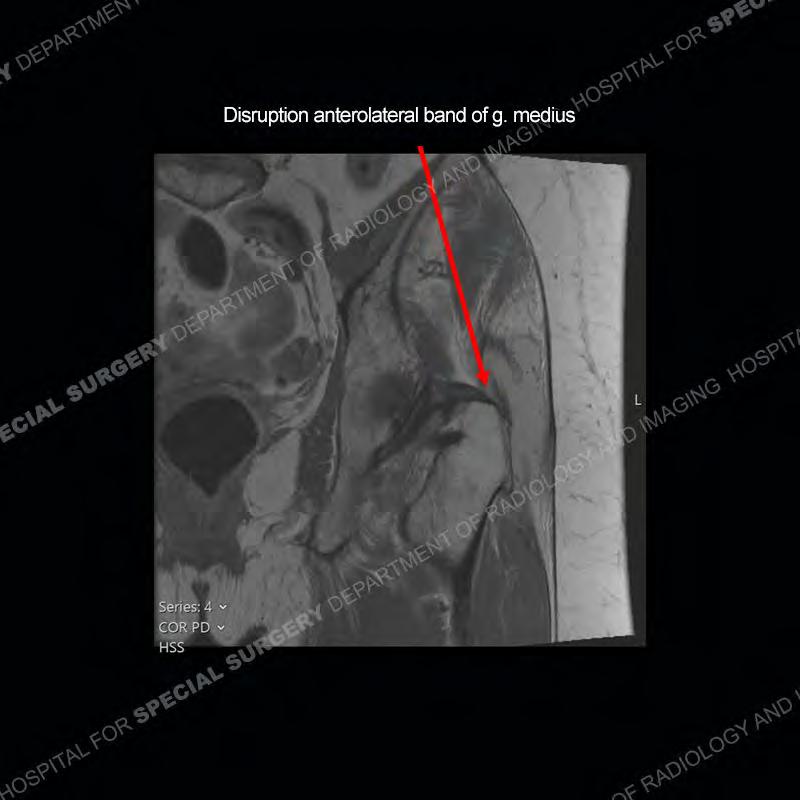

The radiograph is not particularly contributory in this case. The MRI demonstrates markedly abnormal architecture of the gluteus minimus and anterolateral band of the gluteus medius. Portions of the tendons are high signal, portions are highly attenuated, and portions are disrupted. A large, complex fluid collection is present in the adjacent soft tissue.

Diagnosis: Gluteal Tendinosis and Disruption with Complex Trochanteric Bursal Collection

Not as much of a diagnostic dilemma as many of the other cases shown but just a nice example of the pathology seen of the gluteal tendons and a cause of trochanteric pain. Although, frequently thought of in isolation, trochanteric bursitis or bursal thickening is much more commonly a reactive change to underlying pathology of the subjacent gluteal tendons. The gluteus medius is divided into a posterior band and an anterolateral band. Tendinosis and partial tearing very commonly will involve the gluteus minimus and especially the more posterior fibers and then propagate into the anterior lateral band of the gluteus medius. Involvement of the posterior band of the medius is much less common and engenders a marked degree of functional impairment.